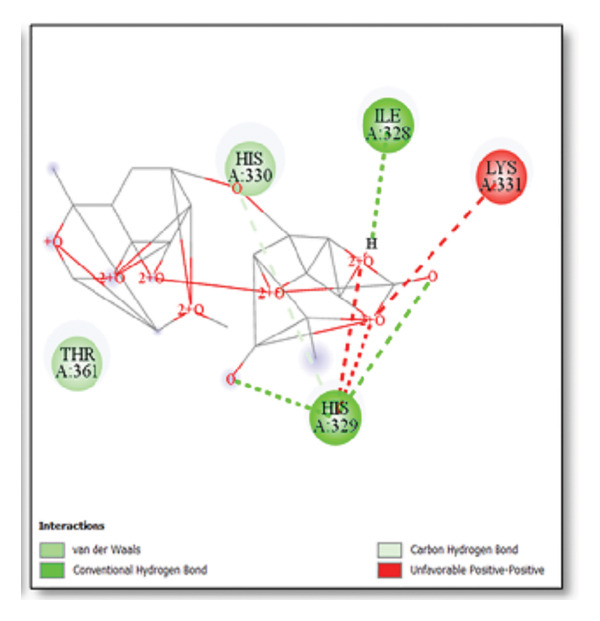

For the tau protein repeat domain, ginkgolide recorded a strong binding energy of −10.63 kcal/mol, with a key stabilizing interaction involving HIS329. This interaction was characterized by a D–A distance of 3.05 Ǻ and an excellent angle of 170.04°. Other top binding compounds included ginsenosides (−6.28 kcal/mol), also interacting with HIS329 and PRO364, and galantamine (−5.47 kcal/mol), forming bonds with VAL337 and VAL339. Berberine bound at −5.33 kcal/mol via GLN351. Apigenin exhibited favorable interaction with the tau repeat domain via a hydrogen bond with ILE 328 (D–A: 2.91 Ǻ; angle 161.21°), highlighting the high quality of the interaction. Among the reference drugs, donepezil bound at −5.34 kcal/mol. Figure 5 details the binding characteristics for tau protein.

Histidine residues are frequently involved in coordinating chaperone‐substrate interactions. The binding of ginkgolide at HIS205 suggests it may stabilize the active conformation of the chaperone, thereby enhancing its ability to bind to and inhibit the formation of amyloid fibrils, a key mechanism reinforced by recent research published [ref. 40]. This research has consistently reinforced that clusterin’s ability to bind to and inhibit the formation of amyloid fibrils is a key mechanism of action, particularly in neurodegenerative diseases. While direct mention of HIS205 is rare, its chaperone function is broadly understood to rely on such key residues. Elias et al. [ref. 41] and Carini et al. [ref. 42] confirm that clusterin’s role in inhibiting aggregation is a major focus of current research. Finally, the predicted binding to HIS329 in tau is highly significant and directly corroborated by recent literature. HIS329 is explicitly located within the microtubule‐binding repeat domain, which is the primary site for tau’s pathological self‐aggregation. Ginkgolide’s predicted binding at this position is a direct mechanism of aggregation inhibition, suggesting it acts as a steric wedge or “capping agent” to prevent the formation of toxic beta sheet structures, aligning with similar strategies explored. Studies have explicitly identified histidine residues within the microtubule‐binding repeat domain as participants in tau’s self‐aggregation process. Hernández et al. [ref. 43] specifically names residues like H329 as being involved in this mechanism. Molecular docking and simulation studies, such as one from 2025 by Saha and Natarajan [ref. 44], also focus on targeting this domain with small molecules to inhibit tau pathology, providing strong support for the in silico predictions.